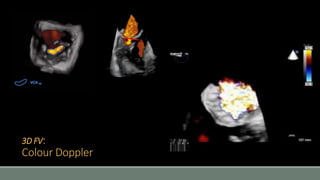

3D FV:

Colour Doppler

• #32 If we want to image the full volume, which means the volume within the whole angle of steering capacity, then it will be constructed from thin volumes acquired during consecutive cardiac cycles. This will need a trigger, typically ECG. Then the sub-volumes will be “stitched” together to produce the full dataset. Obviously this process can create artefact, mainly from respiratory movements and arrhythmia. Once obtained, the 3D full volume dataset is a big chunk of data that can be processed to display different types of views. The last mode is when colour Doppler is superimposed to the 3D pictures, just like it happens in 2D imaging.

• #39 Finally, colour Doppler data can be added to the 3D volume views, to offer a more complete view of the blood flows and jets across the valves.

• #40 Potentially, 3D can offer a better view of the anatomy of the jets, that would otherwise be assumed to be circular and may be underestimated. Complex jets can be properly visualized, for example complex paravalvular leaks.